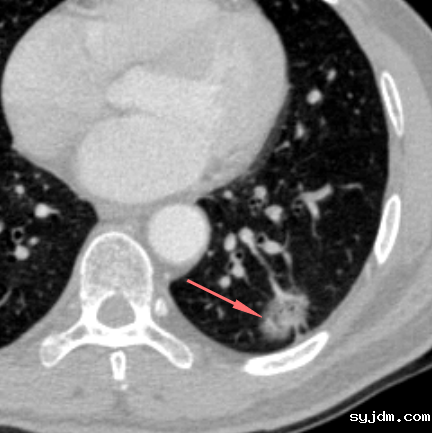

医生阅读CT图像后,将肺内有阳性意义的结节(通常肺窗结节长径超过了5mm)分成良性结节、恶性结节与未定性结节。未定性结节通常需要复查,科学随访尤为重要,复查的时间并不是机械性地定为3个月、6个月、一年等间隔,而是要测量病变的倍增时间(即病变体积增加一倍的时间)来评价病变变化的速度,根据病变直径或体积随时间的变化绘制病变的生长曲线等方法,观察病变的变化规律,明晰病灶的自然进程,尽量保证患者在随访期的安全,同时关注患者的心理状态,为每一个患者制定个性化的随访方案。

如果是恶性结节,要选择最恰当的时间进行手术,如果是良性或炎性结节,要避免让患者“白挨一刀”。